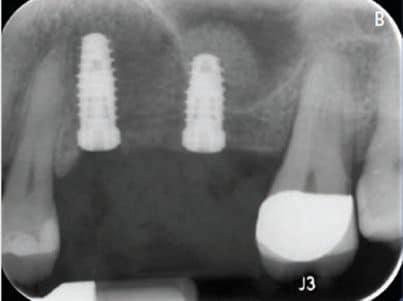

Return to "Implant Placement With Augmentation and Osteotomy Sinus Elevation" sinus-fig-9b Next Previous